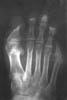

Остеолиз - полное рассасывание кости без последующего замещения другой тканью, вернее, с образованием фиброзной рубцовой соединительной ткани.

Остеолиз обычно наблюдается в периферических отделах скелета (дистальные фаланги) и в суставных концах костей.

На рентгенограммах остеолиз выглядит в виде краевых дефектов, что является основным, но, к сожалению, не абсолютным отличием его от деструкции.

Рис. 12. Остеолиз фаланг пальцев стопы.

Причиной остеолиза является глубокое нарушение трофических процессов при заболеваниях центральной нервной системы (сирингомиелия, табес), при поражении периферических нервов, при заболеваниях периферических сосудов (эндартериит, болезнь Рейно), при отморожениях и ожогах, склеродермии, псориазе, проказе, иногда, после травм (болезнь Горхэма).

При остеолизе исчезнувшая кость никогда не восстанавливается, что так же отличает его от деструкции, при которой иногда возможна репарация, даже с образованием избыточной костной ткани.